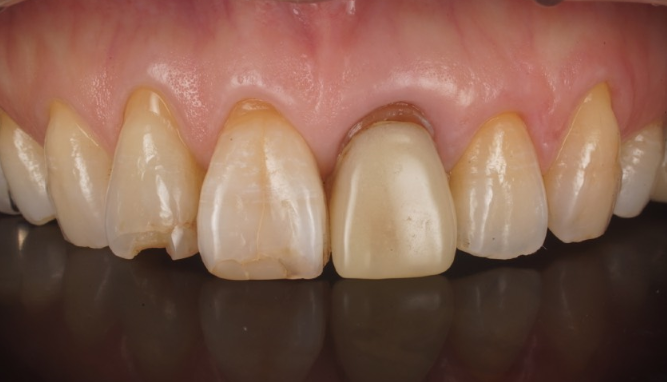

症例3

| 項目 | 詳細 |

|---|---|

| 患者様データ | 40代 男性 |

| 来院時の主訴 | 「前歯を歯磨きすると痛いし、出血する。」 |

| 医院の診断 | 右上中切歯根尖性歯周炎、歯周病 |

| 通院期間 |

6か月 |

| 来院回数 | 10回 |

| 治療費 | 総額:歯周病治療に関しては保険適用診療。その他:370,000円(税抜) 【内訳】 歯周病治療(歯周病検査・歯磨きや生活習慣指導・歯石取りクリーニング) その他、精密根管治療 70,000円、ファイバーポストコア 20,000円、セラミック治療 140,000円×2 |

| リスクと副作用 | メインテナンスが必要、正しい歯磨き習慣が必要不可欠 |

| ここがこだわりのポイント!☝ | こちらは中等度の歯周病と虫歯を併発されていた患者様です。日々の歯磨き習慣を見直していただき、正しいブラッシング法を身につけたことで健康な歯肉を取り戻しました!短期間での治療を希望されていたので審美的な歯肉ラインの獲得はできませんでしたが、健康的な歯肉を獲得できました。 |